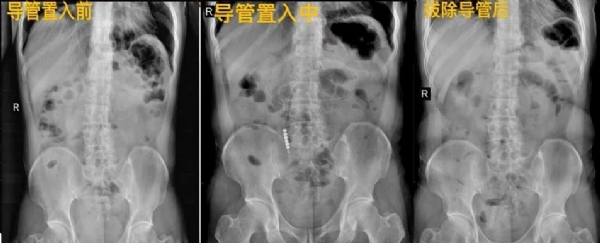

近期一位患者因持续腹痛伴恶心呕吐来诊,行腹部CT检查,考虑肠梗阻,收住院后予以胃肠减压、灌肠等治疗后,效果一般,仍感腹痛,复查腹部平片见阶梯状液平面,结合患者既往肠梗阻术后30余年,结肠肿瘤术后3年,考虑患者有粘连型肠梗阻可能,常规保守治疗效果不佳,经与患者家属沟通后,建议行内镜手术治疗。后在麻醉科和市中院区内镜中心的支持下,为患者行内镜下肠梗阻导管置入术,整个手术操作顺利,约30分钟,术后继续中西医治疗,患者病情很快好转,腹部平片等检查未见异常,恢复正常饮食,出院后回访患者诉无腹痛等不适,已正常饮食活动等。

经鼻肠梗阻导管是一种非血管介入技术,用于引流和减压肠道内容物,长度达3米。导管可以随着肠道蠕动到远端小肠,甚至抵达肛门口,可以有效吸引肠道内容物,减轻肠道压力,加快恢复肠道通畅。尤其对于低位小肠梗阻患者,肠梗阻导管的引流效果优于胃管。